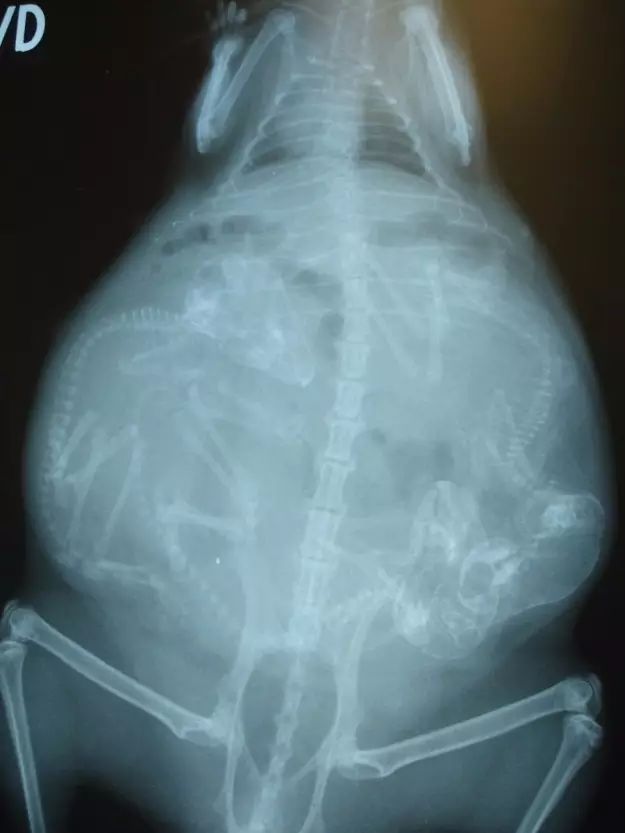

3. 猫咪。